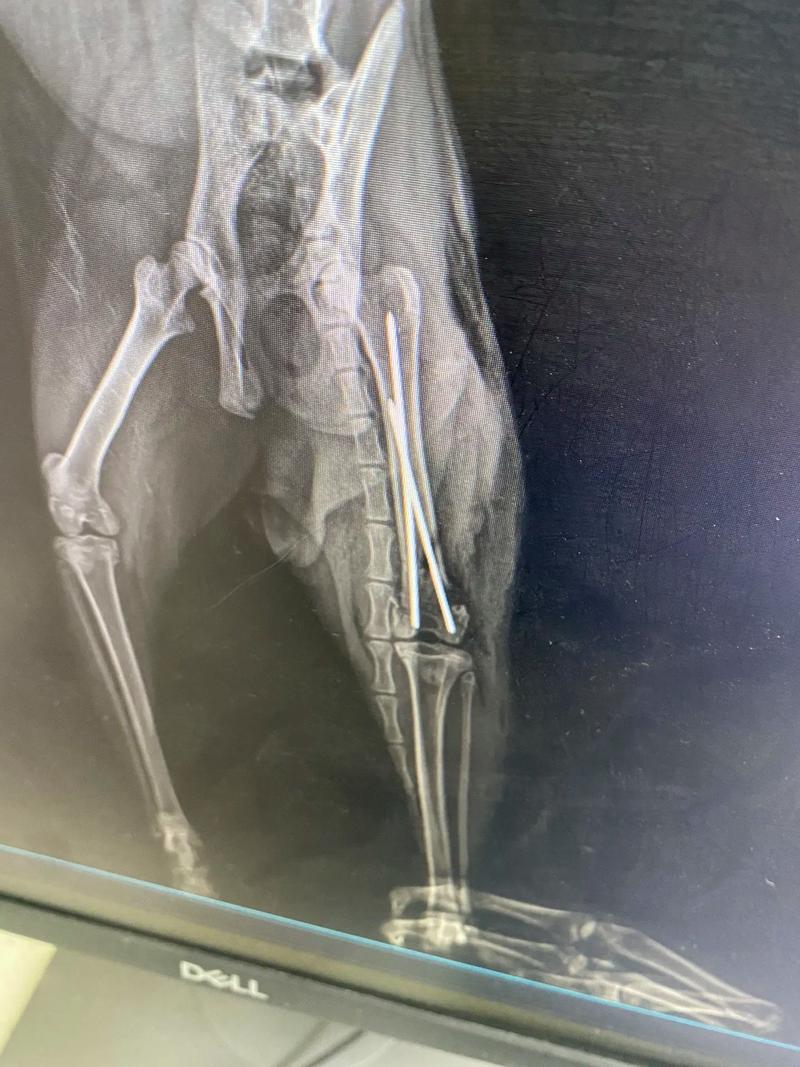

- X光檢查: 這是診斷骨折最關鍵的工具。會拍攝不同角度的X光片,以確認骨折的類型(如閉鎖性、開放性、粉碎性等)、位置、嚴重程度,以及是否有關節脫臼或骨骼內其他病變。

- 骨內固定: 在骨髓腔內置入髓內釘或鋼絲,支撐骨骼兩端。

- 骨板與螺釘固定: 將金屬骨板和螺釘固定在骨折兩端,提供堅固的支撐。適用於複雜或需要強大穩定性的骨折。

- 骨外固定: 透過皮膚將固定器連接到骨頭外部,用於開放性或感染風險較高的骨折。可視癒合情況調整或拆卸。

- 鋼絲或環紮術: 用於固定某些小塊骨折或加強其他固定方式。